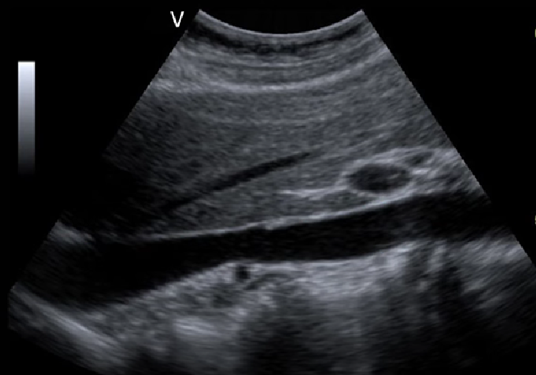

<p>In this sagittal view, what is the structure in this image?</p>

In this sagittal view, what is the structure in this image?

Celiac Trunk